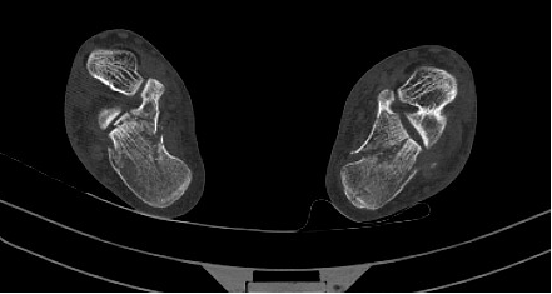

随州首例!市中心医院微创精准修复“粉碎的脚跟”